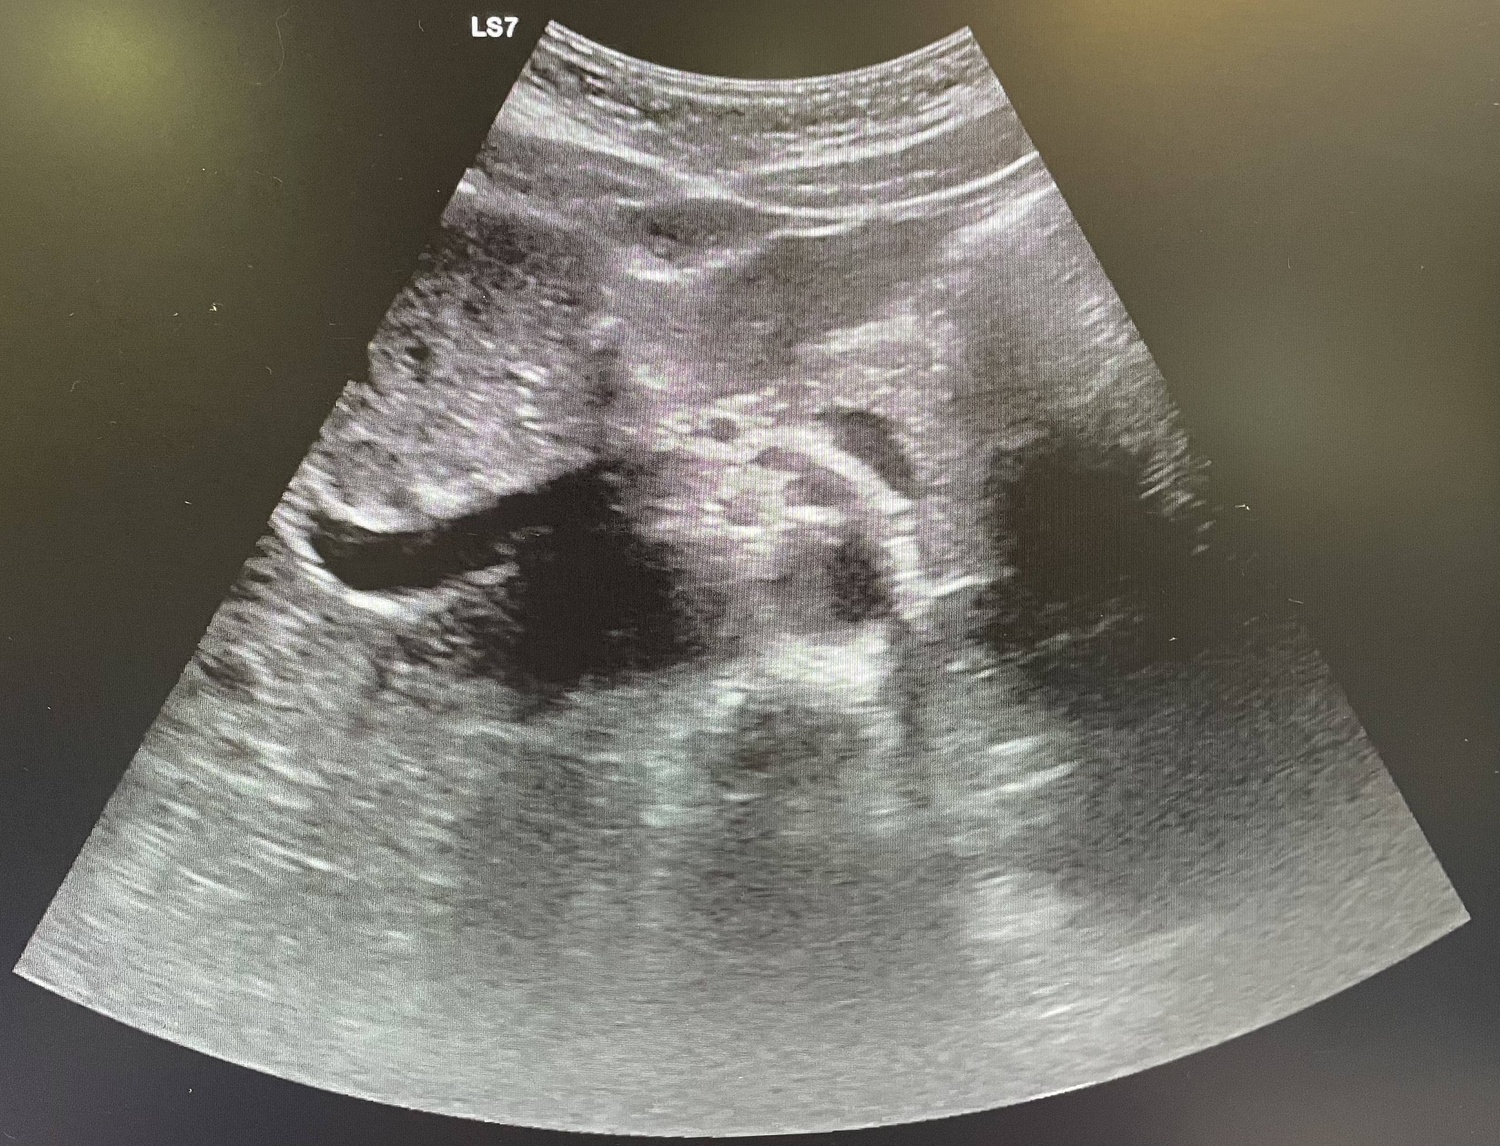

Se realiza analítica con aumento de reactantes de fase aguda (leucocitos 18.00 y PCR 108) y se indica ecografía abdominal que resulta no concluyente, por lo que se procede a alta.

Al día siguiente vuelve con la misma sintomatología, el dolor no cede con analgesia habitual. En la exploración Blumberg claramente positivo, se solicita analítica (leucocitos 13.000 y PCR 127) y se repite ecografía de abdomen que se sigue informando como no concluyente para apendicitis aguda.

La paciente vuelve a acudir a urgencias con la misma sintomatología por lo que decide realizar TAC donde se observa apendicitis evolucionada, se contacta con cirugía que ingresa al paciente por plastrón apendicular.